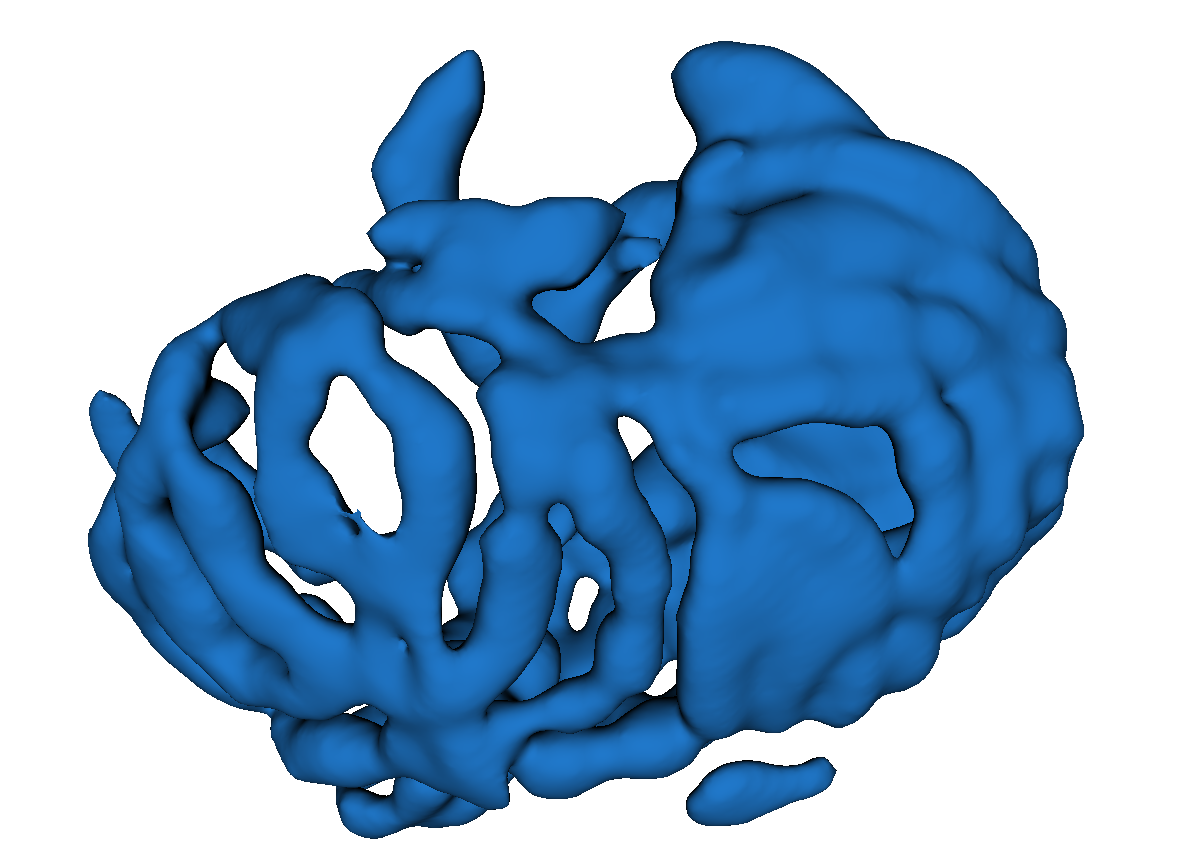

Fig. 3 shows example segmentation results. The proposed method eliminates false positives on the large bowel by the help of the applied topological constraint. Fig. 4 further clarifies the effectiveness of the proposed method by presenting 3D rendered segmentations. The proposed method produces a more topologically correct segmentation of the small bowel with fewer false positives. Fig. 5 presents example barcode diagrams, which again show the reduced numbers of connected components and holes within the segmentation result of the proposed method.

A

B

C

D